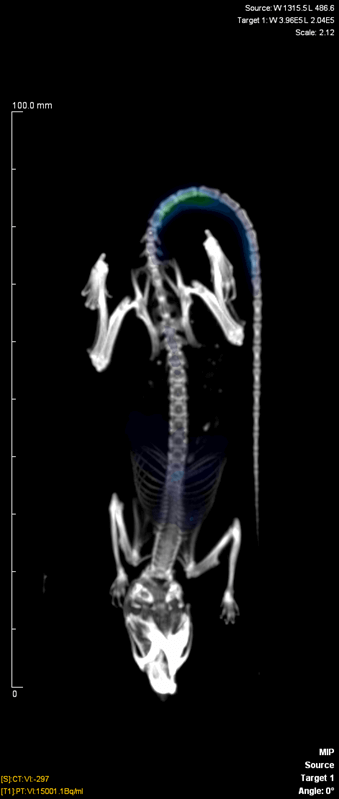

- Le travail concerne la production du 44mSc/44Sc : ciblerie, extraction et purification, étude de l’effet de l’énergie de recul et du «post-effect» sur le complexe 44mSc-DOTA dans le but de concevoir un générateur in vivo de 44mSc/44Sc. Nos travaux ont mis en évidence que la meilleure cavité chélatante du scandium est le DOTA. Aussi, le radiomarquage du DOTA avec le couple 44mSc/44Sc a été optimisé à travers une étude physico-chimique systématique (cinétique, pH, température, rapport métal-ligand). La transition 44mSc / 44Sc ne conduit pas à un décrochage du scandium vers la phase aqueuse. Des peptides conjugués au DOTA (DOTATOC, DOTATATE, IMP-288 …) ont été étudiés. Les constantes d’interaction entre les protéines et le scandium doit être déterminées afin de pouvoir prédire leur spéciation in vivo. Un couplage CE-ICP-MS a été développé et testé avec succès pour les actinides trivalents et des ligands polyamicopolycaroxyliques. L’étude de ces peptides permet également d’obtenir une réponse biologique (biodistribution, premières images TEP…) sur la faisabilité du générateur. Enfin, le développement de cibles de scandium de plus haute activité est indispensable. Il nous permet dans un premier temps, de valider le concept de générateur in vivo, en étudiant la chimie sous rayonnement lors des différentes étapes d’extraction et de purification (notamment sur les résines échangeuses). De plus hautes activités rendent possibles les injections chez le petit animal (images TEP et biodistributions) et les études pré-cliniques pour ce nouveau radiopharmaceutique.